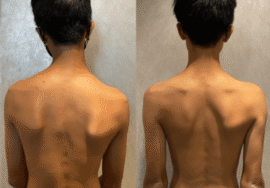

اعوجاج العمود الفقري أو الجنف هو انحناء جانبي غير طبيعي للعمود الفقري يظهر غالبًا في مرحلة المراهقة. تختلف شدة الانحناء وفقًا لزاوية كوب:

ما الأعراض التي قد تشير إلى وجود اعوجاج العمود الفقري؟

عند الأطفال:

عدم تساوي الكتفين.

بروز لوح كتف أكثر من الآخر.

ميل في الحوض أو اختلاف طول الساقين.